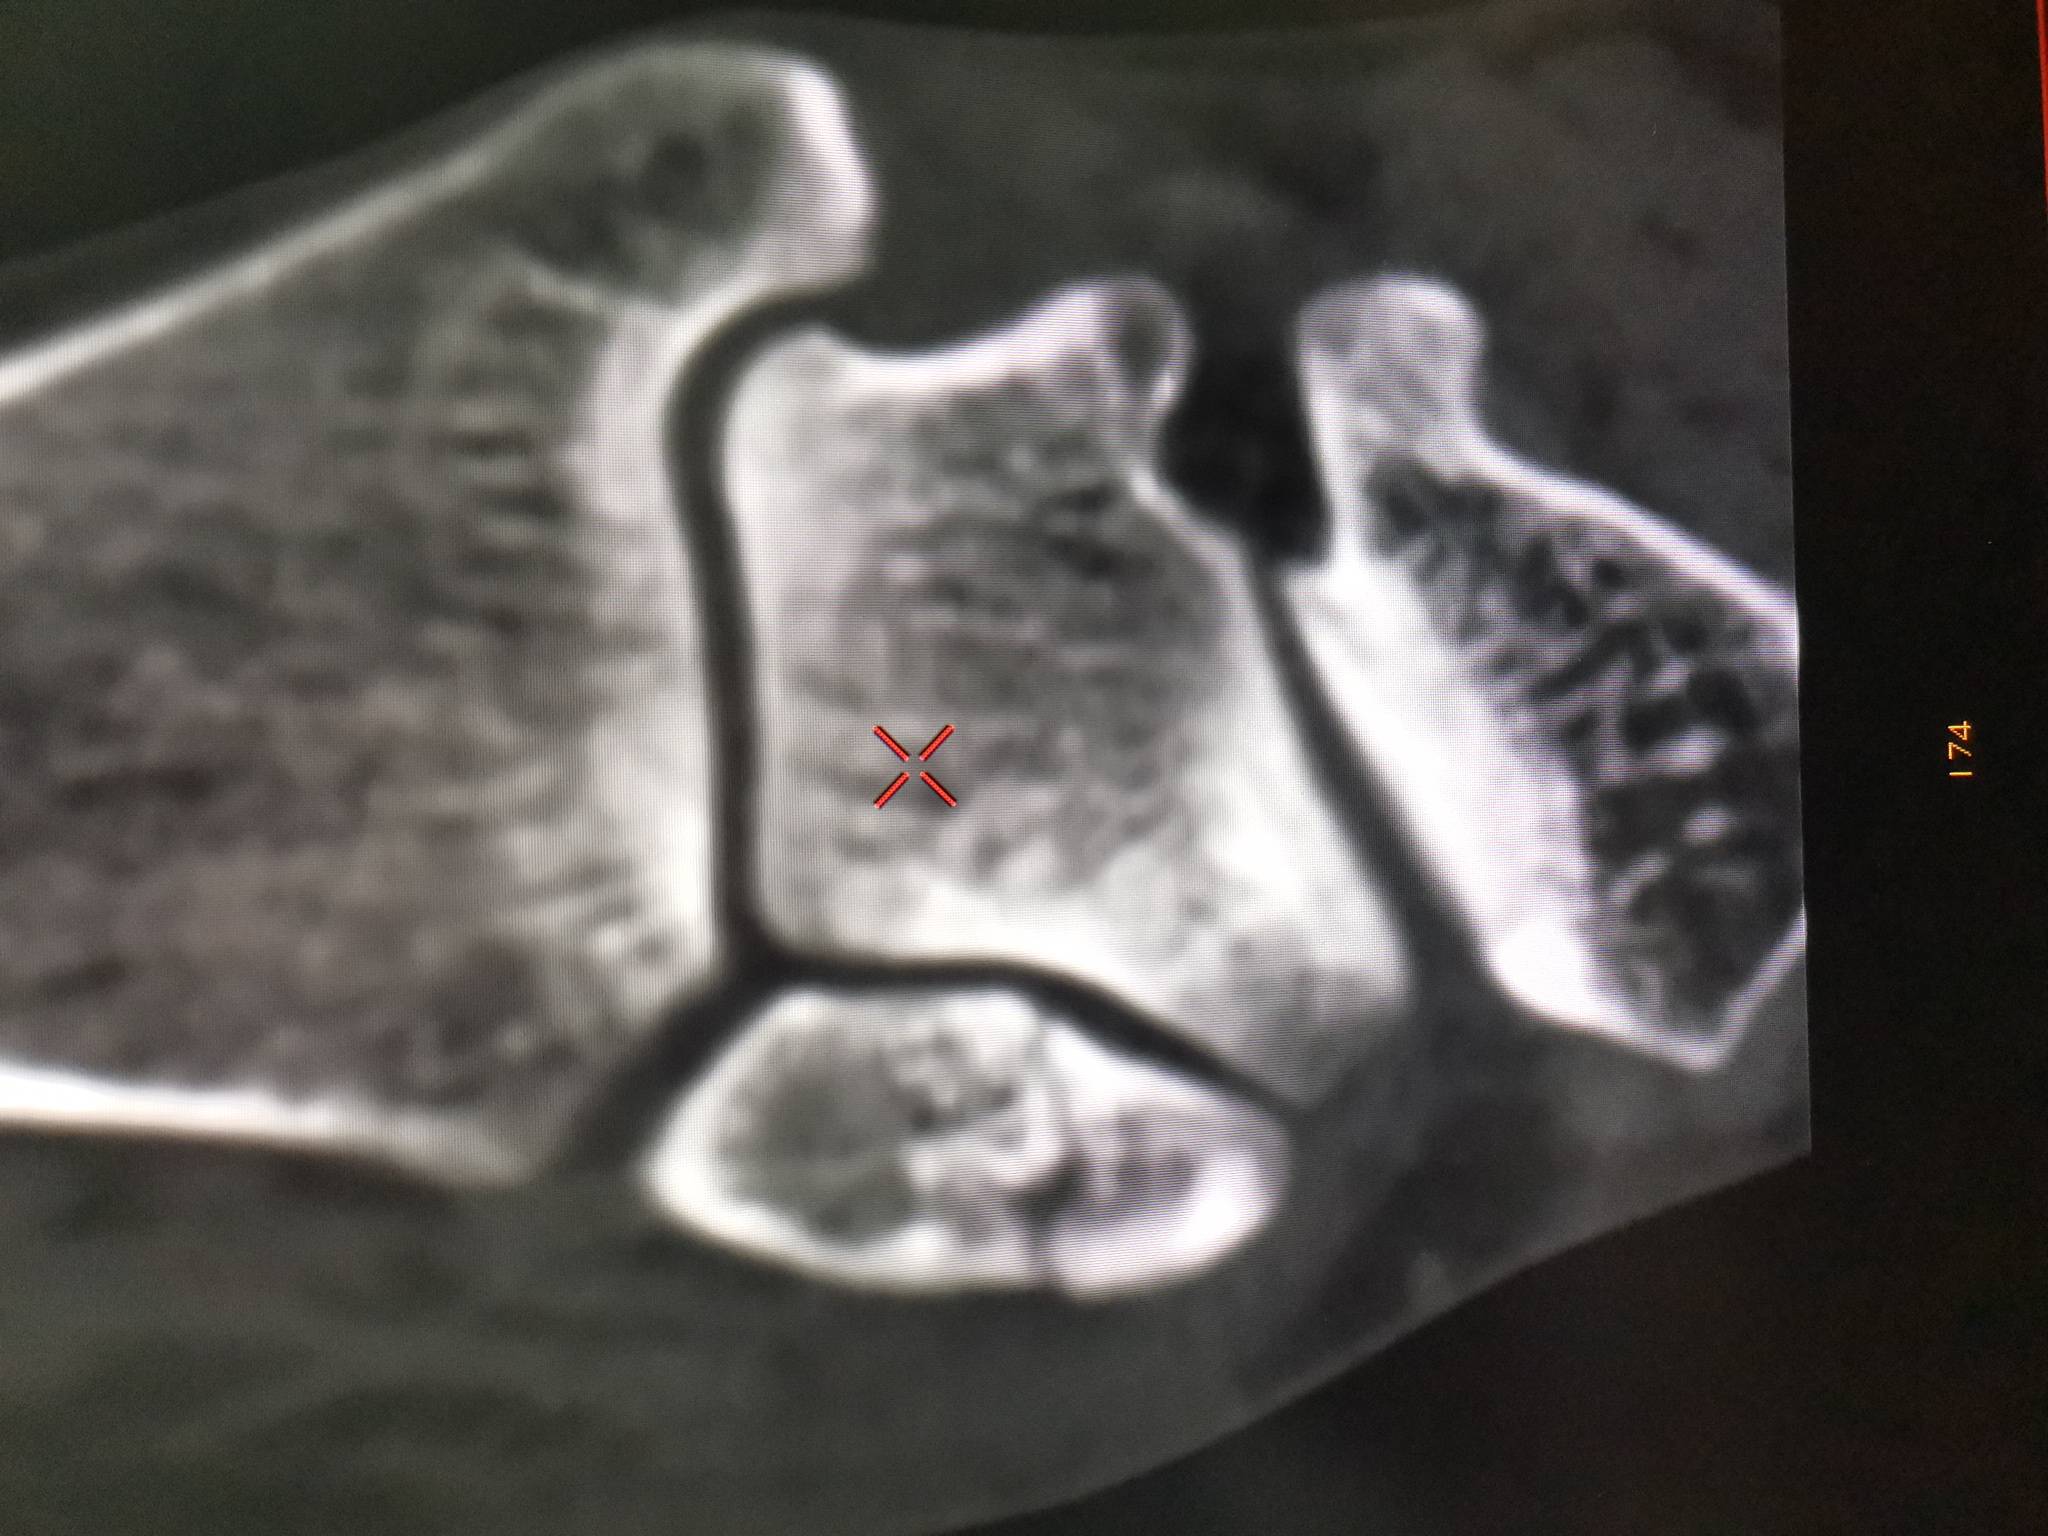

昨晚打羽毛球,崴脚了。今天早上拍了DR和CT,哦豁,骨折了。

现在已打石膏。